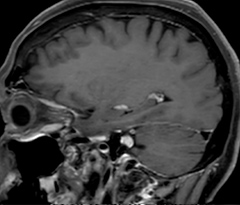

A two year follow-up scan of a CPA meningioma using both Ingenia 3.0T without CS and Ingenia Elition 3.0T with Compressed SENSE allows for a nice comparison to demonstrate the protocol improvements achieved on the Elition: 3D FLAIR has a shortened scan time, improved SNR and still the same spatial resolution. BrainView (3D T1 TSE) has improved spatial resolution and SNR with shortened scan time. For 3D T2 Drive the spatial resolution has been improved. 3D THRIVE used to have an interpolated 0.8 mm slice thickness, but true thickness at 1.6 mm, so that axial slices displayed a decent quality, but reformats were suboptimal. Compressed SENSE is used on Elition to improve spatial resolution and reduce the non-interpolated slice thickness to allow smoothly reformatted images. Total scan time (adding SmartBrain and an additional b2000 diffusion) was 13:19 on Ingenia, and is now reduced to 10:42 on Ingenia Elition.

Ingenia 3.0T (without Compressed SENSE)

3D FLAIR 1.0 x 1.0 x 1.0 mm* 4:24 min.

3D TSE T1w 1.0 x 1.0 x 1.2 mm* 2:40 min.

3D T2w Drive 0.8 x 0.8 x 1.0 mm* 3:05 min.

3D T1w THRIVE 0.8 x 0.8 x 1.6 mm* 1:30 min.

Ingenia Elition 3.0T with Compressed SENSE

3D FLAIR 1.0 x 1.0 x 1.0 mm* 2:50 min.

3D TSE T1w 1.0 x 1.0 x 1.0 mm* 2:10 min.

3D T2w Drive 0.7 x 0.7 x 0.7 mm* 2:52 min.

3D T1w THRIVE 0.7 x 0.7 x 0.8 mm* 1:30 min.

*true voxel size, without interpolation